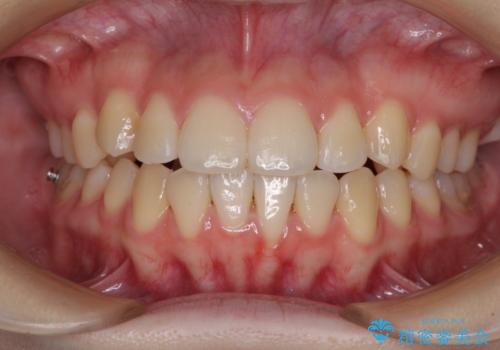

カリエール・ディスタライザーとインビザラインを用いた八重歯の改善

- 前歯の叢生と上顎左右の八重歯を気にして来院された患者様です。

奥歯の咬み合わせを見ると、左側は上顎が下顎に対して相対的に前方にあり、上下の前歯が接触していない状態でした。

咬み合わせを改善するためには、左側上顎臼歯を後方に移動させた咬み合わせにする必要があります。

インビザライン単体で改善することも可能性もありますが、インビザライン単体で達成する可能性が低いと考えられたため、カリエール・ディスタライザーという補助装置を併用して、より確実性を上げることとしました。

奥歯の咬み合わせを改善しながら、並行してインビザラインで歯列を整えることとしました。

カリエールディスタライザーを併用したことで、左側臼歯の咬み合わせを確実に改善させることができました。